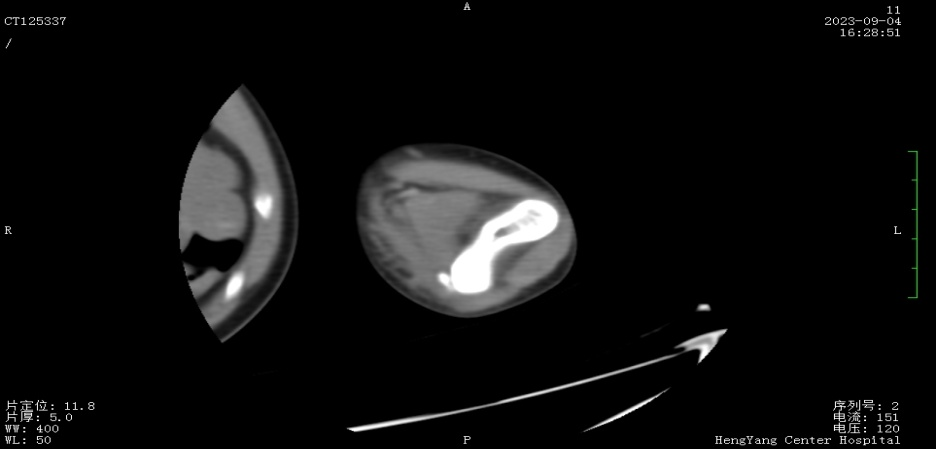

接診后,醫(yī)師發(fā)現(xiàn)小莫同學(xué)的左肘關(guān)節(jié)自然狀態(tài)下僅能伸展至約115°,并伴有習(xí)慣性屈肘。經(jīng)與骨科醫(yī)生溝通并閱片后,考慮骨化肌炎,針對(duì)這種情況,一般采取手法松解關(guān)節(jié)和關(guān)節(jié)功能鍛煉相結(jié)合的治療方案。但此方案常用于成人患者的關(guān)節(jié)粘連傳統(tǒng)松解術(shù)和關(guān)節(jié)松動(dòng)訓(xùn)練,對(duì)于兒童來說刺激強(qiáng)度太大,且因兒童骨骼及關(guān)節(jié)較成人脆弱,無法保證治療的連續(xù)性及安全性,一味采取輕柔手法,不僅治療時(shí)間長、見效慢,還可能加重后續(xù)治療難度。

首次治療結(jié)束后,小莫同學(xué)的左肘關(guān)節(jié)即可伸展至145°。9月19日,小莫同學(xué)已結(jié)束第一階段共14次治療,他的左肘關(guān)節(jié)就可以自然伸展至170°,可滿足上肢基本功能需求。